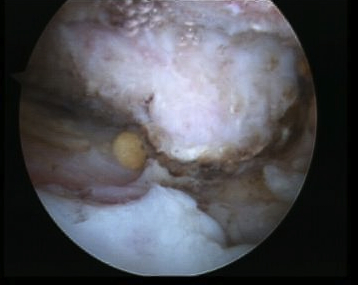

Arthroscopic acromioplasty

Technique

Beach chair / lateral

- posterior viewing portal subacromial space

- lateral working portal

- bursectomy with shaver

- electrocautery to release / resect CA ligament

- use burr to perform anterior acromioplasty

CA ligament above shaver and cuff

Large acromial spurs

Spur resection